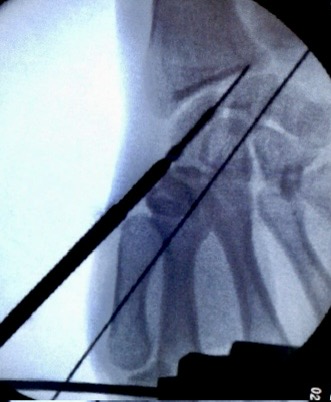

xx 男 36岁 腕舟骨骨折 掌侧切开复位内固定术 。

术前X片显示舟骨腰部骨折

术前X片显示舟骨腰部骨折,AO分型B2型。

掌侧入路

Herbert钉固定